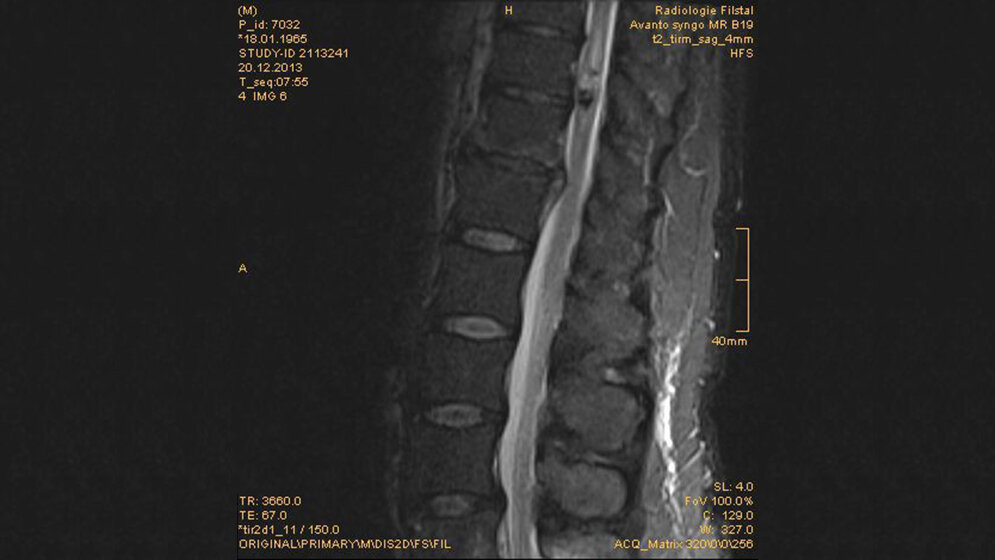

Tumoröse Veränderungen: Intramedulläres Kavernom

Spinale intramedulläre Kavernome zeigen entweder eine akute zunehmende neurologische Schädigung oder schleichende neurologische Defizite. Die chronisch progressive Myelopathie ist Folge der Hämorrhagie und resultierenden gliotischen Reaktion. Patienten mit intramedullären Kavernomen profitieren weniger von der chirurgischen Therapie als solche mit einer intraduralen extramedullären oder intravertebralen Lokalisation der Läsion.